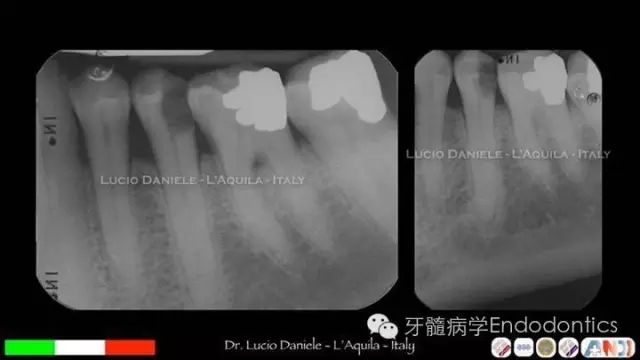

圖5.隨訪2年、4年、10年